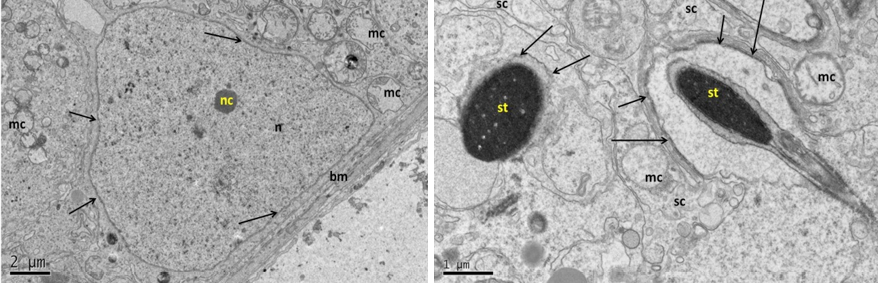

Electron micrograph (TEM) of Sertoli cell from fresh control group (A)

Electron micrograph (TEM) of spermatogonia (Left) and spermatocyte (Right) from group (B) cryopreserved with freezing media